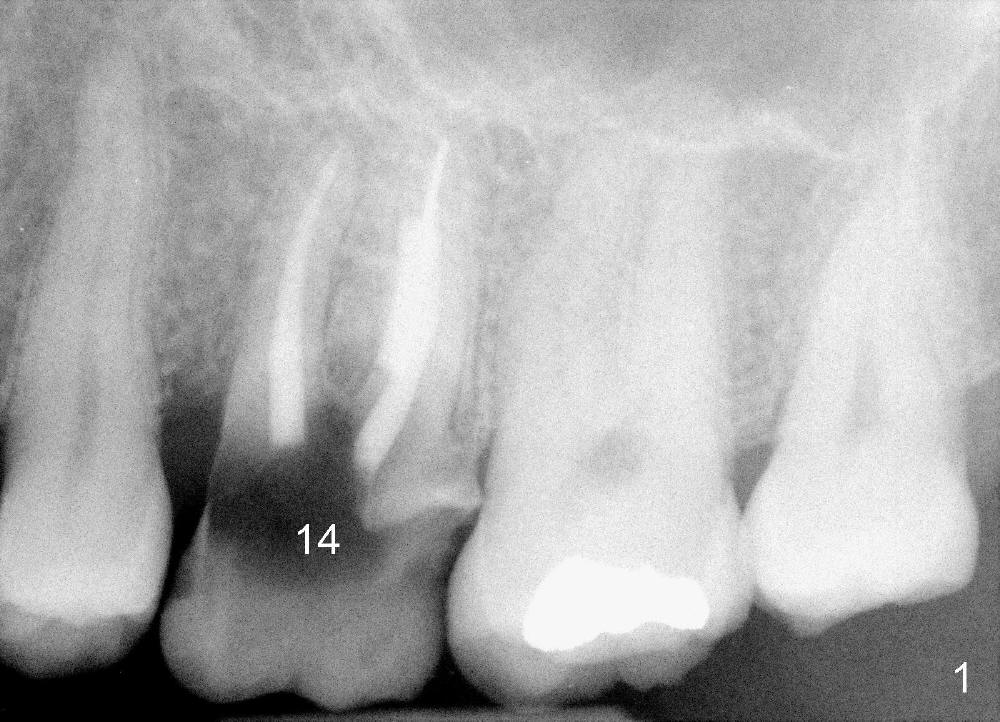

The 1st approach is used for the following case: a 46-year-old man with #14 (Fig.1). The root stumps are large and relatively close to each other (Fig.2 mirror view) so that when the roots are extracted (Fig.3 black), the septum is narrow (white). A 1.2 mm pilot drill penetrates the septum (red).